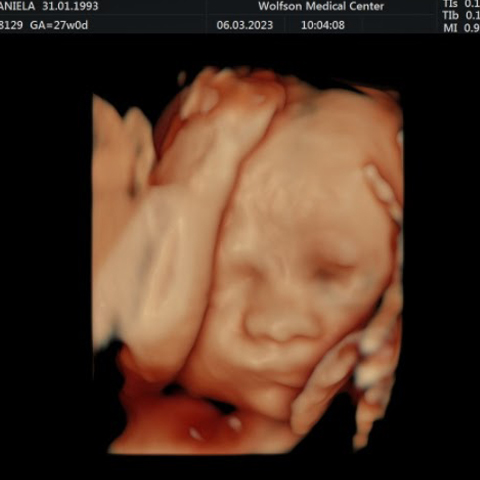

אין להשכח שבסוף הכל רק דברים קטנים. תמיד יש אפשרות לקפוץ לבדיקת יתר או דימות, רק כדי לוודא שהכל נקי ובסדר